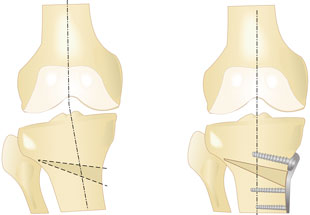

In den letzten 15 Jahren ist das Konzept der so genannten Umstellungsosteotomie entscheidend weiterentwickelt worden, sodass dieses Knorpeloperations-Verfahren seinen Schrecken verloren hat. Das Vorgehen ist in diesem Fall folgendermaßen: Es wird zunächst eine genaue Diagnostik mittels Röntgen vorgenommen, diese erfolgt mit Hilfe einer so genannten Achsaufnahme des gesamten Beines im Stand. Anhand dieser Aufnahme wird die Fehlstellung sowohl innen oder außen am Kniegelenk genau ausgemessen. Dann wird ausgemessen, wie durch ein kleines aufbiegendes Verfahren am Schienbeinkopf (häufigste Vorgehensweise) oder durch eine Einkerbung des Oberschenkelknochens (selteneres Verfahren) die Achse entsprechend der Stelle, an der die Verschiebung am Bein vorhanden ist, bei der Knorpeloperation wieder korrigiert werden kann. Durch neu entwickelte Instrumente handelt es sich dabei nicht mehr um ein Verfahren, wo der Knochen zum Beispiel am Schienbein komplett durchgeschnitten werden muss, sondern es erfolgt mehr oder minder eine Einkerbung des Knochens und der Knochen wird etwas aufgebogen. Damit der Knochen sich nicht sofort wieder verschließt, wird eine kleine Metallplatte angebracht, die den Knochen offen hält.

Aus dem Knochenmark kommen Zellen, die in der Lage sind, neuen Knochen zu bilden und so verknöchert dieser nun in der richtigen Position. Etwa 2 Tage nach der Knorpeloperation kann der Patient aus dem Krankenhaus entlassen werden, eine Teilbelastung an Gehhilfen von ca. 3 bis 6 Wochen ist notwendig bis der Knochen genügend Stabilität bekommen hat.